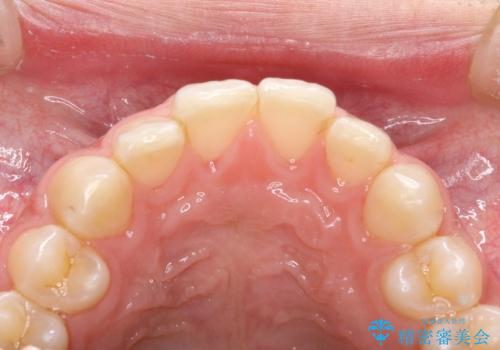

茶渋による着色と下の前歯の裏側のべったり歯石

コーヒーやお茶をよく飲む患者様で、その影響か全体的に茶渋が見られました。

下の前歯は少しがたつきがあるため、歯石がたまりやすいように見られます。

着色落としをメインに歯石も落とすためPMTC(エアフロー)にて施術いたしました。